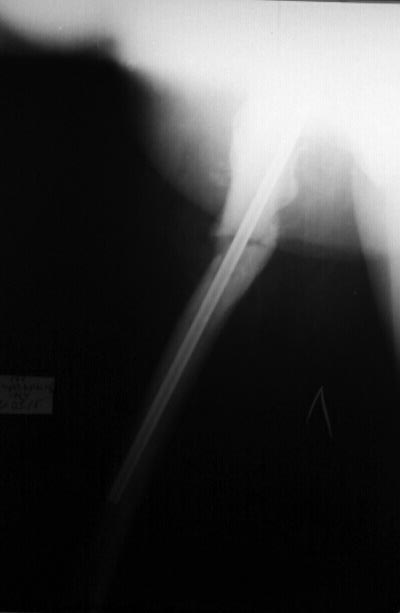

Re: мраморная болезнь

Уважаемые коллеги, больную готовим к операции совместно с эндокринологом и терапевтом (диабет, анемия). Кстати сделали снимок в боковой проекции